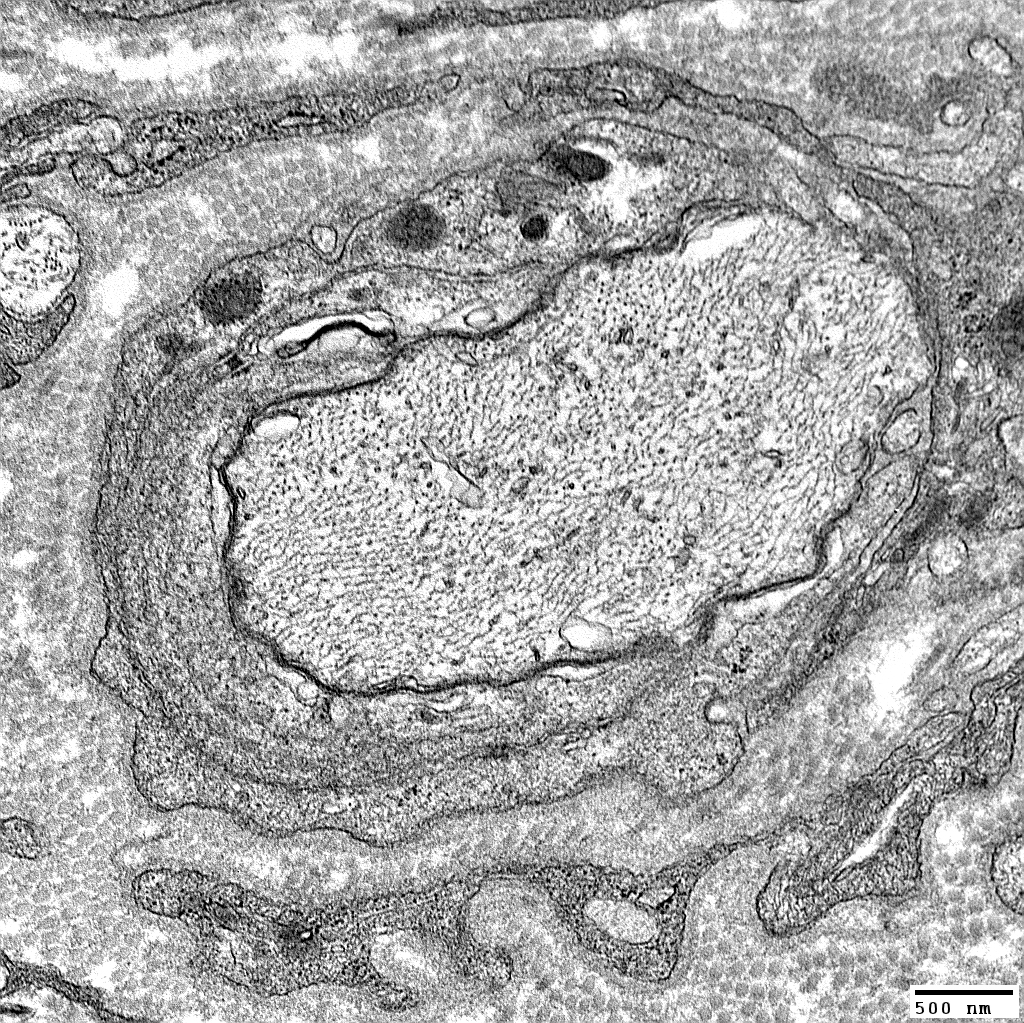

Cells within Onion Bulbs

From: Robert Schmidt MD

|

Schwann cells & Macrophages within onion bulb layers

Macrophage: Between onion bulb layers